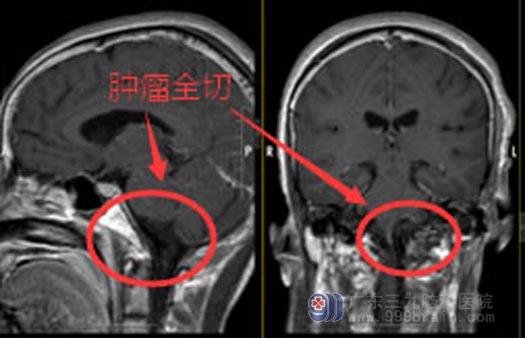

患者有手术指征,经过准确的术前诊断和周密的术前准备后,鲁明带领团队在全麻下为秦阿姨行“左侧舌下神经管跨颅内外沟通舌下神经鞘切除术+左侧乙状窦结扎术+硬脑膜修补术+颅骨成形术”。术中见肿瘤根部位于左侧舌下神经管,位置深在,周围结构复杂,暴露难,突破舌下神经管与颅内外沟通;在显微镜下将肿瘤全切,术中电生理监测面听神经、舌咽神经、迷走神经、副神经均保留完好。手术顺利,复查CT未见出血。术后病理回报:富细胞性神经鞘瘤。

术后第二天,秦阿姨即神志清醒,言语对答切题,能遵嘱活动,视力、视野正常,双侧鼻唇沟对称,伸舌居中,无明显面瘫,四肢肌力Ⅴ级,感觉、肌张力基本正常,生理反射存在,很快就可以出院了。